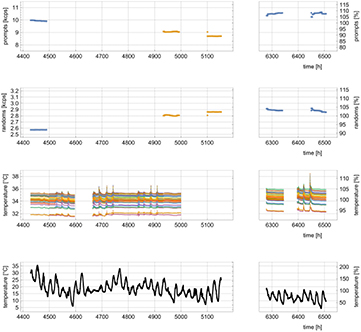

For the generation of the individual ACF values, it is necessary to acquire an object scan and a blank scan. In order to register all possible coincidences from the 176Lu isotopes, the energy windows must be widened to  and the energy autocorrection must be disabled since the correction algorithm requires the presence of the 511 keV photopeak, which is neither present in the LSO blank scan nor in the LSO object scan. The energy autocorrection normally compensates for the drifts in the measured γ-ray energy spectra, caused by the temperature dependence of the APD gains (Hamamatsu Photonics 2004). For the measurement of ACFs with 176Lu background activity, particularly long acquisition intervals of between hours and days are required. An excessive temperature drift, without autocorrection of the energy spectrum, could lead to varying prompt random count rates and, as a consequence, to biased ACF estimates. In anticipation of this issue, object scans were acquired during two weekends and blank scans were acquired during three weekends to verify the stability of count rates over long measurement intervals. During each weekend, a total of 16 frames with a duration of 4 h (64 h in total) of LSO coincidence data were acquired. Furthermore, the temperature of the 32 PET cassettes was measured with temperature sensors located inside the PET cassettes. In addition, in order to identify potential correlations, the outdoor temperature at the research centre was also measured. In addition to the prompt count rates and random count rates for the individual PET cassettes for all frames, the total prompt count rates and total random count rates of all measurement frames, for both the blank scan and the object scan, were also computed.

and the energy autocorrection must be disabled since the correction algorithm requires the presence of the 511 keV photopeak, which is neither present in the LSO blank scan nor in the LSO object scan. The energy autocorrection normally compensates for the drifts in the measured γ-ray energy spectra, caused by the temperature dependence of the APD gains (Hamamatsu Photonics 2004). For the measurement of ACFs with 176Lu background activity, particularly long acquisition intervals of between hours and days are required. An excessive temperature drift, without autocorrection of the energy spectrum, could lead to varying prompt random count rates and, as a consequence, to biased ACF estimates. In anticipation of this issue, object scans were acquired during two weekends and blank scans were acquired during three weekends to verify the stability of count rates over long measurement intervals. During each weekend, a total of 16 frames with a duration of 4 h (64 h in total) of LSO coincidence data were acquired. Furthermore, the temperature of the 32 PET cassettes was measured with temperature sensors located inside the PET cassettes. In addition, in order to identify potential correlations, the outdoor temperature at the research centre was also measured. In addition to the prompt count rates and random count rates for the individual PET cassettes for all frames, the total prompt count rates and total random count rates of all measurement frames, for both the blank scan and the object scan, were also computed.

3.1. Scanner stability

The measurements of the PET cassette temperatures revealed no relevant temperature fluctuations. All cassette mean temperatures remained between  and

and  , with minimal and maximal standard deviations of

, with minimal and maximal standard deviations of  and

and  , respectively. Two factors that caused major changes in the cassette temperatures were identified. The first rise in temperature, of up to

, respectively. Two factors that caused major changes in the cassette temperatures were identified. The first rise in temperature, of up to  over the average, lasted a number of hours and was due to intervention by the persons inside the scanner room during examinations done with the MR-BrainPET. The second was due to seasonal temperature changes that affected the climate of the building and led to mean temperature differences of ≈

over the average, lasted a number of hours and was due to intervention by the persons inside the scanner room during examinations done with the MR-BrainPET. The second was due to seasonal temperature changes that affected the climate of the building and led to mean temperature differences of ≈ C between measurements done in July and in September. Cassette temperature values and outdoor temperatures are shown in figure 7. Apart from the short temperature peaks and the long term variation caused by seasonal changes, the temperature of the cassettes remained constant within <

C between measurements done in July and in September. Cassette temperature values and outdoor temperatures are shown in figure 7. Apart from the short temperature peaks and the long term variation caused by seasonal changes, the temperature of the cassettes remained constant within < minimum to maximum. Prompt and random count rates from 176Lu radiation that were registered during these measurements are shown in figure 7. The count rates measured over single weekends were very stable and observed maximum variations were not larger than 3.6%. The count rates of measurements from successive weekends varied from 3.6% to 4.4%. When the measurements were separated by months, variation in the count rates reached up to 12%. These large changes in the count rates seem to be correlated to the observed change of cassette temperature due to seasonal temperature fluctuations. The observed periods of a few hours with increased cassette temperature do not appear to have influenced the measured count rates, since during the blank and object scan, no personnel were present in the scanner room.

minimum to maximum. Prompt and random count rates from 176Lu radiation that were registered during these measurements are shown in figure 7. The count rates measured over single weekends were very stable and observed maximum variations were not larger than 3.6%. The count rates of measurements from successive weekends varied from 3.6% to 4.4%. When the measurements were separated by months, variation in the count rates reached up to 12%. These large changes in the count rates seem to be correlated to the observed change of cassette temperature due to seasonal temperature fluctuations. The observed periods of a few hours with increased cassette temperature do not appear to have influenced the measured count rates, since during the blank and object scan, no personnel were present in the scanner room.

Figure 7. From top to bottom: 1: prompt count rates for blank (blue) and coil (yellow) measurements. 2: Random count rates for blank (blue) and coil (yellow) measurements. 3: Temperature values of the 32 PET cassettes logged during the measurements of the blank scans and the object scans. 4: Outdoor temperature during time of measurement at Research Center Jülich.

The very low natural activity of Lutetium requires very long transmission scan times and therefore very stable count rates. Without any objects inside the MR-PET FOV, i.e. no γ-photon emitter apart from 176Lu, the prompt and random count rates can only be affected by the thermal stability of the scintillation detector. An average prompt count rate of 8.9 kcps was measured with the Tx/Rx head coil in the FOV and a count rate of 10.3 kcps was measured without the coil. Thus, approximately 1400 photons per second were absorbed by the coil, and generation of ACFs from 176Lu with a Poisson noise component, that is comparable to routine emissions scans, requires an acquisition time of several days. The system temperatures were found to be very stable inside the PET cassettes during the acquisitions of both the blank and the object scans and were within a range of  peak to peak. Over several months, an additional general temperature drift of all cassette temperatures of

peak to peak. Over several months, an additional general temperature drift of all cassette temperatures of  was observed and was found to be correlated with a substantial change in the outdoor temperature. In agreement with these temperature variations, count rates for prompts and randoms are subjected to larger variations when the measurements are separated by longer times. Apart from a few exceptions, variations in count rates over one week remained below 1%. In all cases, they were smaller than 3.6%. Since this small variation was found to affect the counts in all LORs similarly, it mainly introduces a bias in the AC corrected images. Calibration of the PET scanner for using Lu-coil-AC in the routine image reconstruction can effectively compensate this bias. Nevertheless, in order to minimise differences in the count rates, acquisition of blank and object scans should be done during consecutive days and weekends.

was observed and was found to be correlated with a substantial change in the outdoor temperature. In agreement with these temperature variations, count rates for prompts and randoms are subjected to larger variations when the measurements are separated by longer times. Apart from a few exceptions, variations in count rates over one week remained below 1%. In all cases, they were smaller than 3.6%. Since this small variation was found to affect the counts in all LORs similarly, it mainly introduces a bias in the AC corrected images. Calibration of the PET scanner for using Lu-coil-AC in the routine image reconstruction can effectively compensate this bias. Nevertheless, in order to minimise differences in the count rates, acquisition of blank and object scans should be done during consecutive days and weekends.